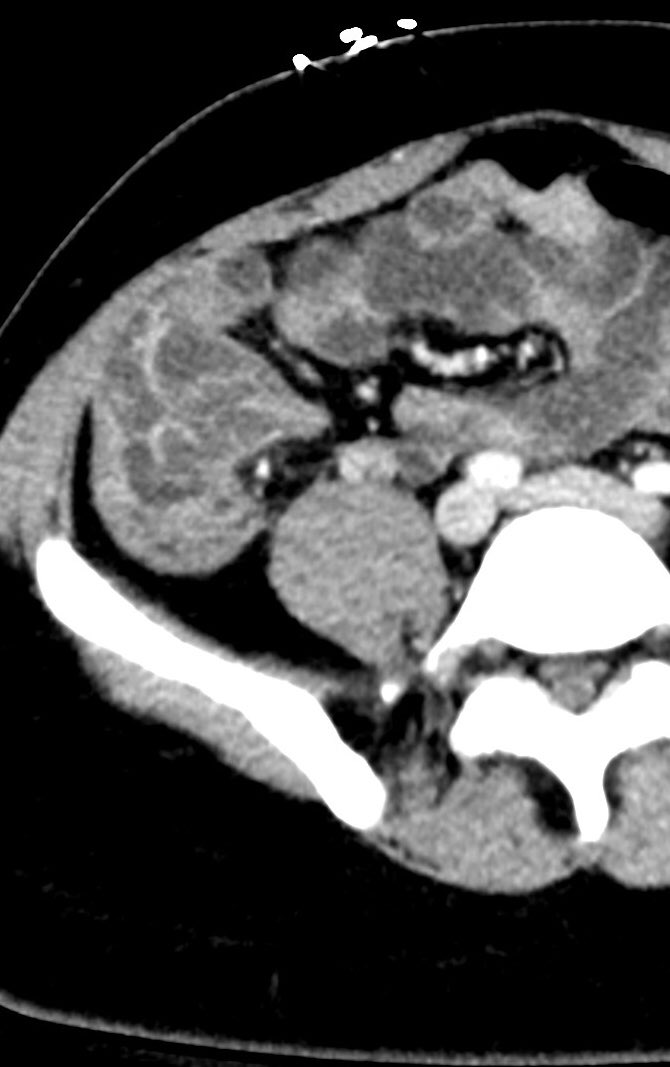

Real time bullet migration! Taken about an hour apart. Fragment sandwiched between visceral and parietal pleura with subsequent migration. Clinically stable until intervention.

#radiology#ct#trauma#chest#radres pic.twitter.com/Jc9XDlNJnT